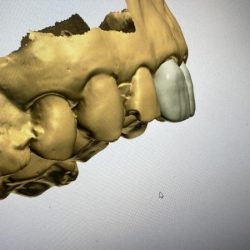

Fotos de Dra Alejandra Mendoza Ortodoncista